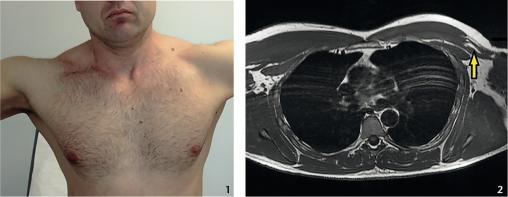

Quatre mois plus tard, il est revu en visite annuelle d’aptitude (fig. 1 ). À l’inspection, l’asymétrie du grand pectoral fait prescrire une IRM (fig. 2 ).

Échographie musculaire ou IRM en urgence précise la désinsertion, partielle ou complète, de l’attache humérale du tendon.